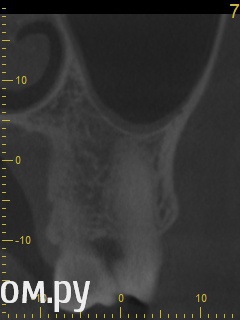

Анатолий М Опубликовано 21 апреля, 2014 Поделиться Опубликовано 21 апреля, 2014 Добрый день. Помогите пожалуйста.17 зуб (верхняя семерка с права). Пол года назад был депульпирован. Все это время присутствуют боли под этим зубом по симптомам очень похожие на кисту (распирание, боль ноющая не сильная, то появляется то сама собой изчезает. при перкуссии 17 зуб слегка болезненный). 2 месяца наза решили зуб перелечить. На ОПТГ ситуация до перелечивания. По снимку видно что первоначальное лечение было проведено плохо. Корни были плохо пройдены и плохо заполены цементом.Месяц хождения с гидроокисью кальция на воде никакого эфекта не дали. Врачи считают что под зубом есть киста. И предлагают удалить зуб. Так как перелечивание не помогло.Прилагаю снимок КЛКТ после лечения. Зуб все еще под временной пломбой. Из трех врачей лишь один разгледел на КЛКТ кисту под 17 зубом. Два других ни на КЛКТ ни на прицельных никакой кисты не видят. Направили к неврологу. Думают что киста если она и есть (в чем они не уверены) не дает имеющихся симптомов.Пожалуйста посмотрите на КЛКТ. Есть ли там киста или нет? И могут ли боли быть от нее?Заранее спасибо. Ссылка на комментарий

Анатолий М Опубликовано 21 апреля, 2014 Автор Поделиться Опубликовано 21 апреля, 2014 КТ до лечения. Эту пломбу вскрыли. Каналы полностью проработали и поставили лекарство. 3 раза меняли по принципу 3дня+3нед+4недели. Ниже приложен КТ контрольный через месяц лечения. Сейчас в каналах лекарство. Кт после постоянного пломбирования корневых каналов? Есть снимки во время лечения и контрольный после? Ссылка на комментарий

Анатолий М Опубликовано 21 апреля, 2014 Автор Поделиться Опубликовано 21 апреля, 2014 Снимок во время лечения делали? Коффердам и оптика использовались? На кт в тех срезах что Вы выложили кисты не вижу Снимки во время лечения делали три раза прицельные с иголками в каналах. Но они остались у врача. У меня их нет. Но она по ним кисты не видела. Коффердам использовали только при первом посещении когда вскрывали старую пломбу и прорабатывали каналы. При последующих посещениях при смене лекарст его не использовали так как кольцо на зубе плохо держалось и постоянно слетало. Плюс травмировало десну.Микроскоп использовали все три раза. По словам врача (врач высшей категории эндодонтист зав отделением):При вскрытии старой пломбы каналы практически не заполены цементирующим составом. Иструмент при вскрытии пломбы в каналы проваливался. Хотя стояла постоянна пломба. Из трех каналов лишь один был проработан до верхушки корня. Два других либо до половины либо на треть. Врачь полностью прошла все каналы и даже залезла за апекс. туда при первом пломбировании врач даже не пыталась лезть. При третьем посещении врач констатировала что каналы чистые. Никаких признаков инфекции нет. И белезненная перкуссия от чего то другого. Специально проводила ревизию каналов при втором и третьем посещении без анастезии что бы понять где болит. Но так и не поняла. Повела на консультацию к профессору в их стоматологи. Посмотрев контрольную КТ он сказал что там киста и надо удалять зуб! Похоже что мой врач с ним не очень согласна, хотя и спорить не стала поэтому отправила меня на консультацию к неврологу. Ниже срезы конрольного КТ после месяца лечения гидрооксидом кальция на воде. Срезы по дуге. Сделал как смог. Шаг срезов как я понимаю 1мм. Линия по перек дуги снимок номер 1 (см нумерацию в конце названия файла) Ссылка на комментарий